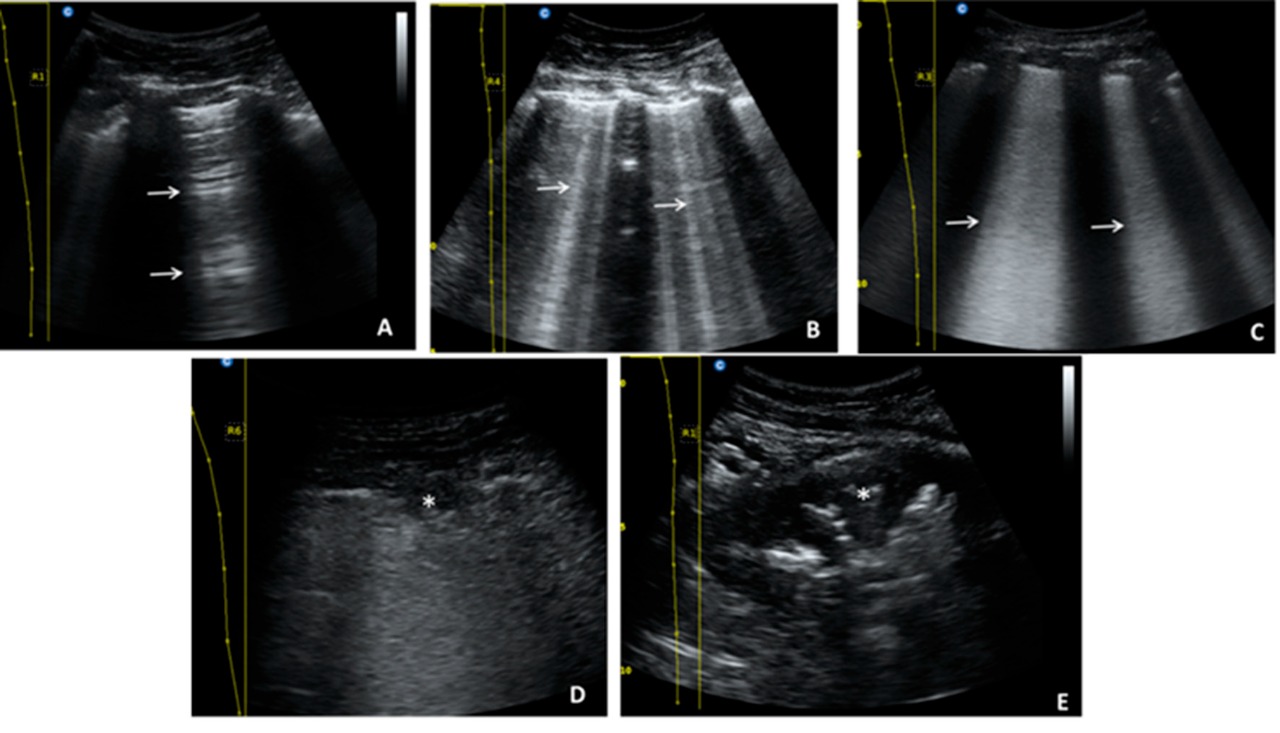

Ecografía pulmonar como predictor de terapia intensiva en neumonía por COVID-19

28 diciembre 2021

En el análisis univariado se observó una asociación entre la puntuación de la ecografía pulmonar (EP), los niveles elevados de procalcitonina y péptido natriurético cerebral y el ingreso a terapia intensiva. En el análisis multivariado solo la puntuación de EP fue un predictor independiente de requerimiento de terapia intensiva. MEDICINA (Buenos Aires), diciembre de 2021